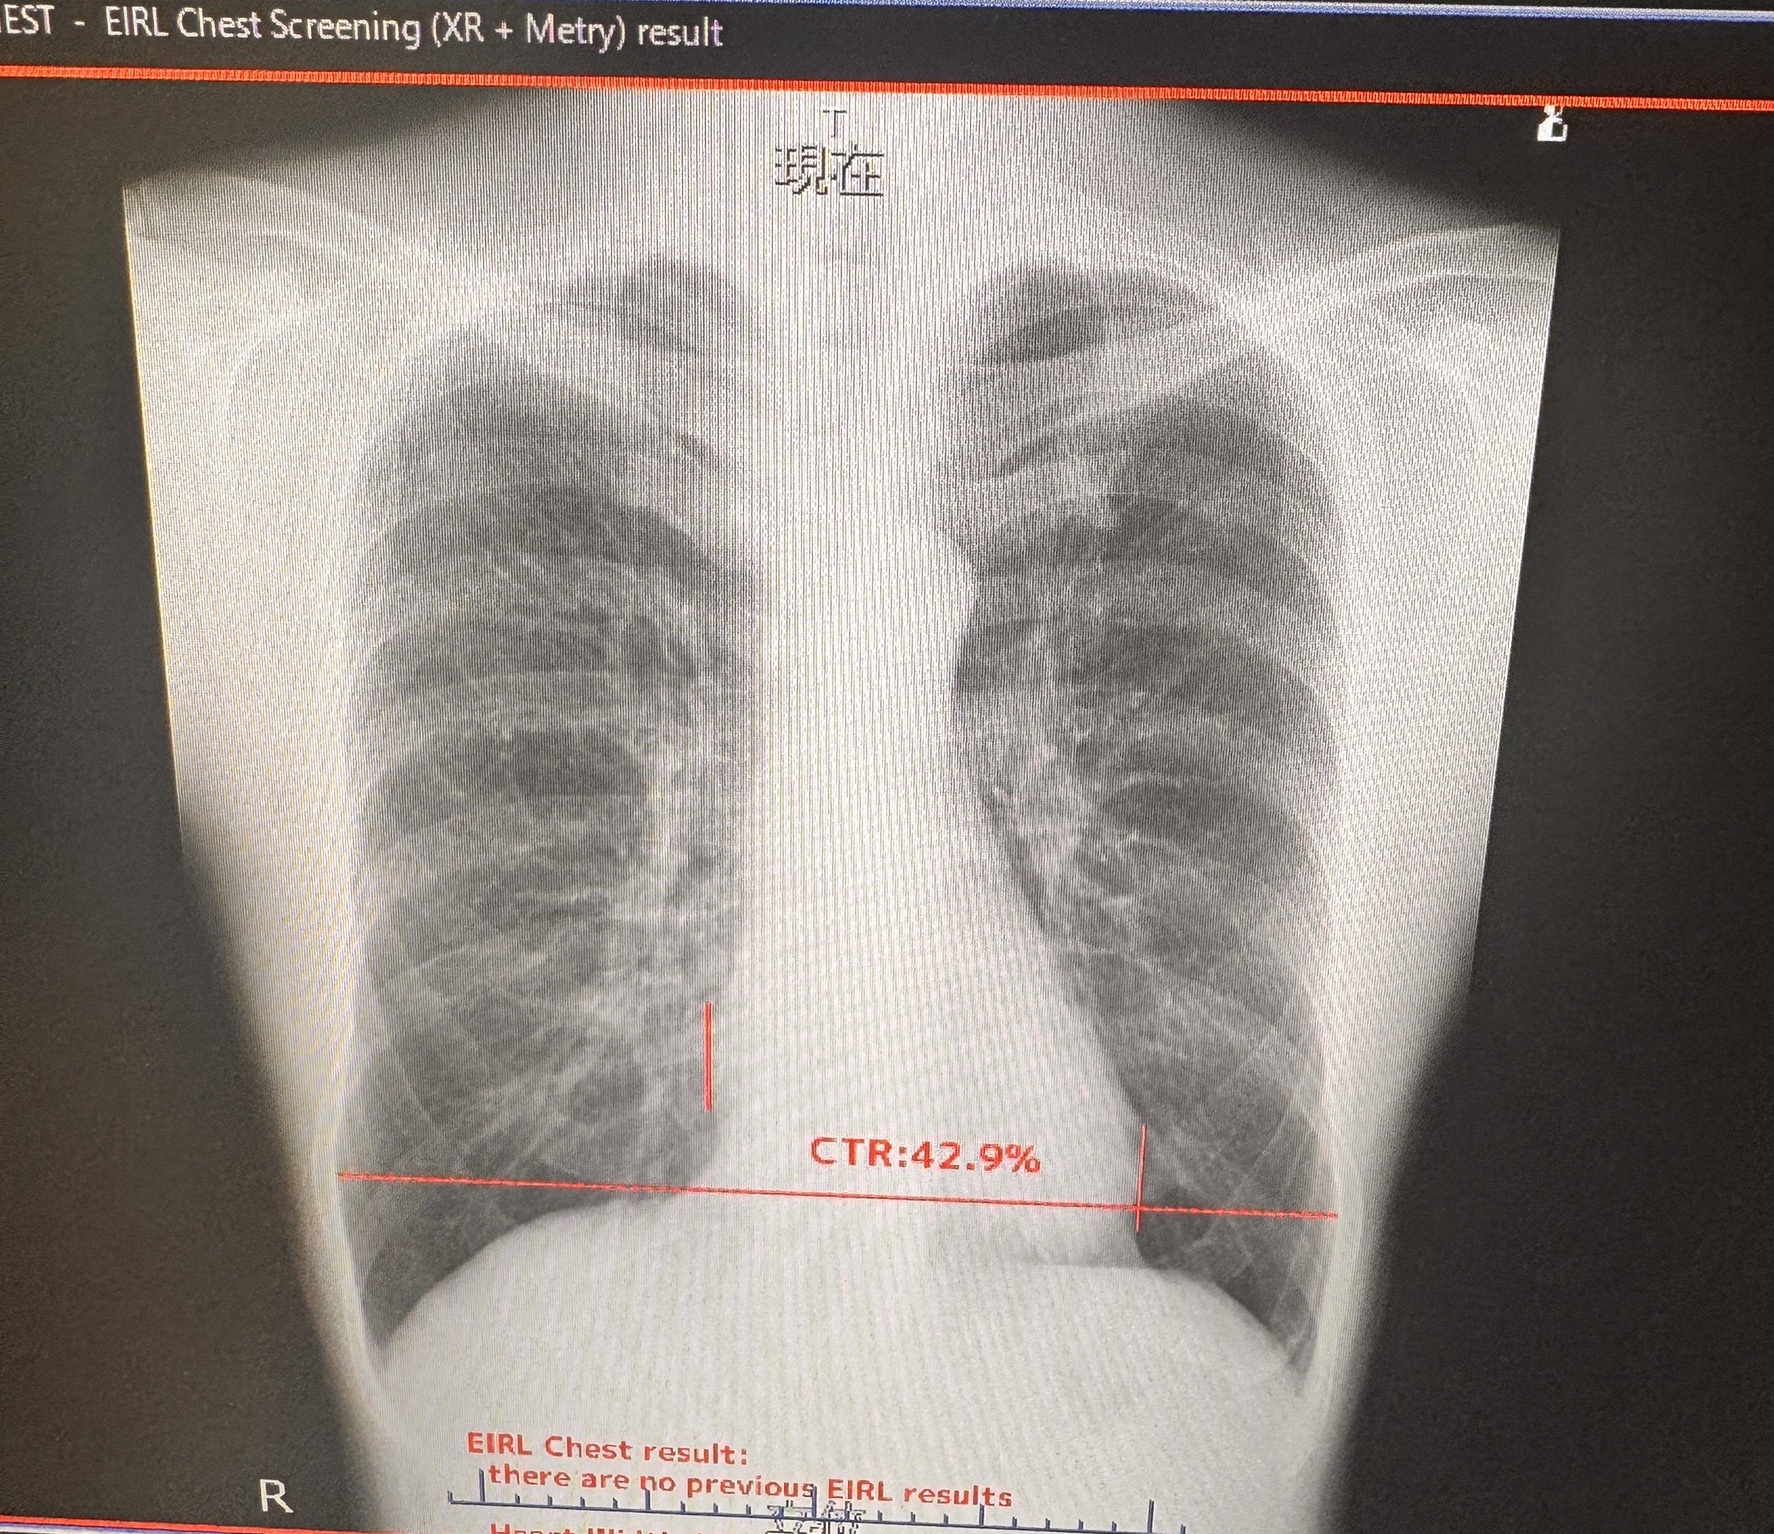

単純レントゲン検査装置

胸部単純レントゲン写真の全例に対してAI読影を行い、トリプルチェックを行うことで見落としのリスクを減らしています(写真は院長の胸部)。